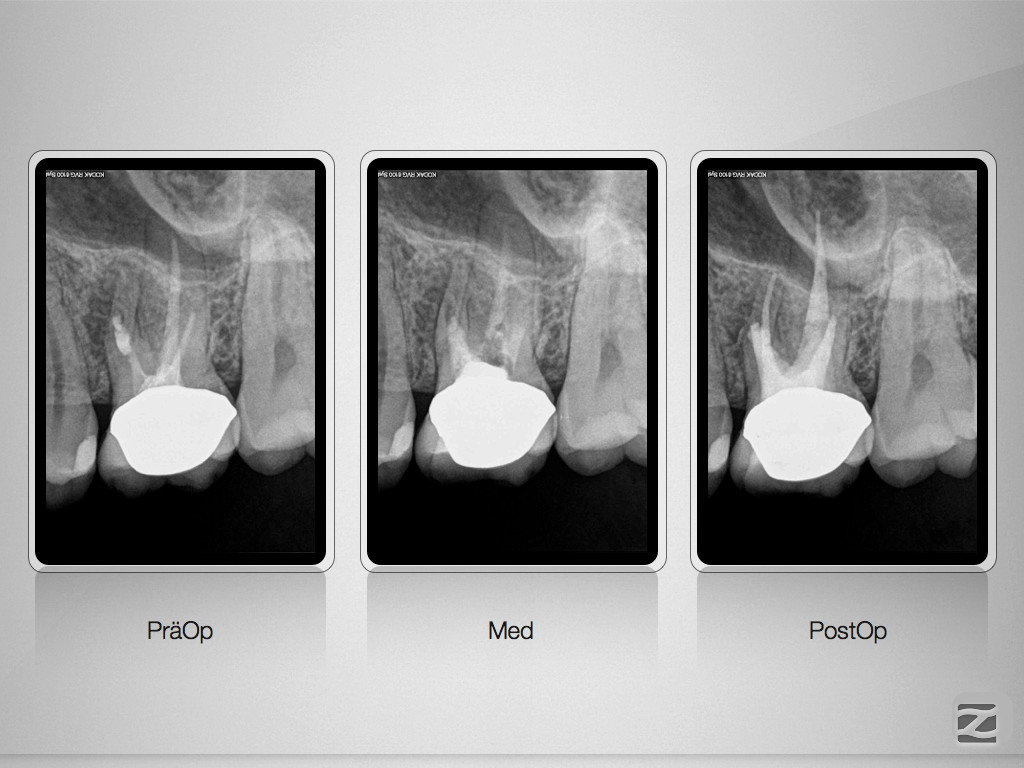

26 Recall 4 Jahre.002 Veröffentlicht 16. Juli 2015 am 1024 × 768 in Wie hoch ist eigentlich die Recall-Rate?